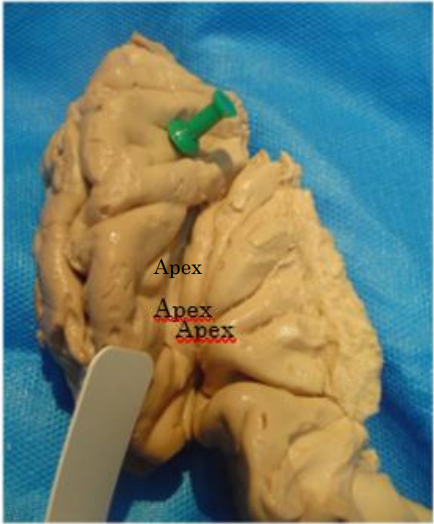

The insula is located deep to the frontoparietal and temporal opercula. If the lateral face of the hemisphere is observed, said cortical region is not visible on its surface, but at the moment in which the opening of the sylvian fissure occurs, the lobe of the insula begins to be observed, called the apex of the insula, when most superficial sector of this lobe (figure 1)3.

Figure 1: inferior view of the lateral aspect of the hemisphere, apex of the insula.